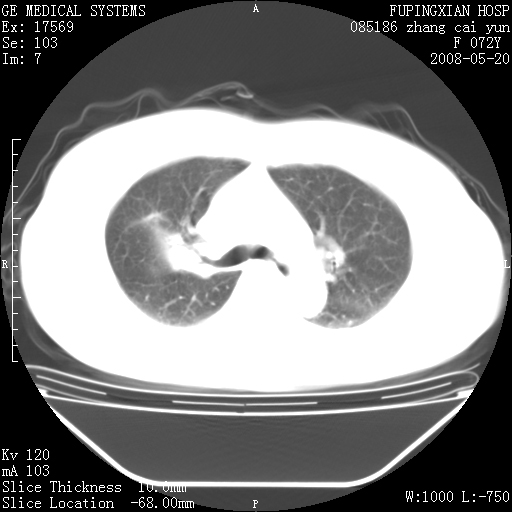

标题: CT13542:发热,咳嗽数日,经抗菌素治疗好转,请大家看排除 [打印本页]

标题: CT13542:发热,咳嗽数日,经抗菌素治疗好转,请大家看排除

上叶支气管略变窄并通畅,内壁光滑。考虑:单纯阻塞性肺炎!

右上叶支气管走行自然,未见明显管壁增厚等征像,另左主支气管起始部可见异常腔道向左侧延展左肺动脉干后方,与左下叶支气管相通,为左下叶支气管变异?

有节段性阻塞性肺炎与不张,近段支气管狭窄,周围散在肿大淋巴结影,以周围型肺癌可能性大,建议纤支镜检查。

右肺上叶实变影,内见支气管充气征,右上叶支气管通畅,肺门区未见软组织密度影,抗炎治疗有效,考虑炎症,建议继续抗炎治疗复查。

右上肺实变,间内有支气管充气征,考虑炎症,建议抗炎后复查